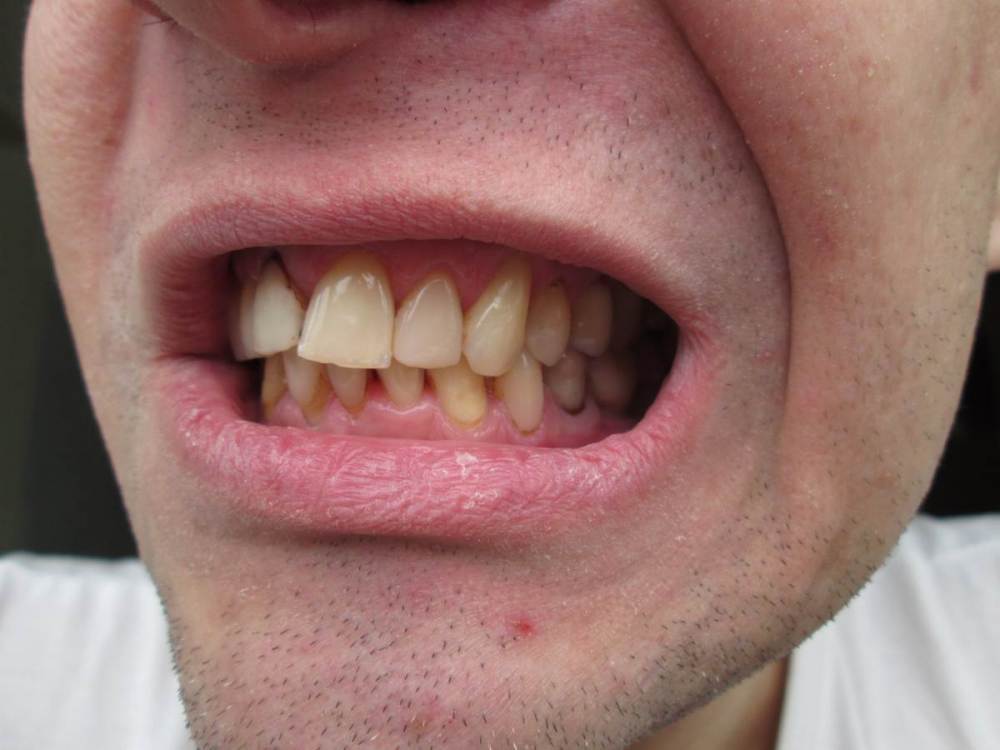

Jonik Опубликовано 24 апреля, 2022 Поделиться Опубликовано 24 апреля, 2022 Здравствуйте! У меня клиновидный дефект, убыль костной ткани и рецессии десны. Было несколько консультаций у ортодонтов, мнения разные: 1) Брекеты ставить нельзя, недостаточно костной ткани, брекеты усугубят ситуацию; 2) Брекеты можно поставить, но результат непредсказуем, можно потерять зубы (передние нижние); 3) Брекеты поставить можно и нужно или будет хуже. Прошу вашего совета как поступить, у меня два вопроса: 1) Нужны ли мне брекеты, помогут ли они в моем случае; 2) Можно ли установить мне брекеты, учитывая объем кости и тд. Есть КТ по ссылке https://drive.google.com/drive/folders/1zs22D5kDglz_UOtPfKQ2lUmh8P5N8cv7?usp=sharing Ссылка на комментарий